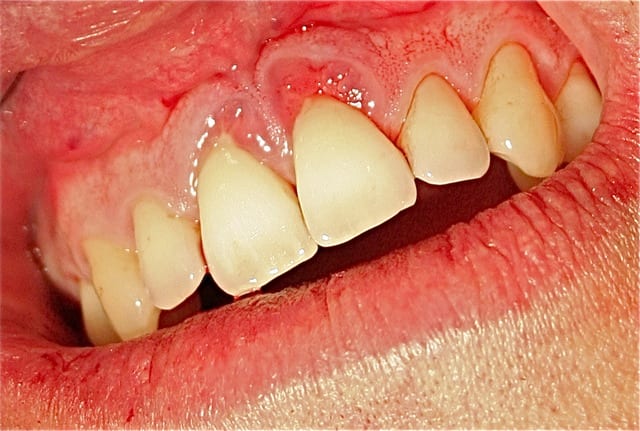

je peux vous soumettre quelques clichés, je crois intéressants ...j'ai investit dans du matériel photo pour vous séduire, acheté des habits sérieux...

toujours aucune extractions depuis 8 ans, sur des cas de paro nommé irréparable par les plus grands parodontistes de France et de suisse! LOL

lus de 250 cas extrêmes et difficiles traités prouvent que nous sommes bien en présence d'une blessure souillée et qu'il suffit de la traiter comme toute blessure souillée.

Les photos que tu montres ne donnent aucun renseignement quand à la guérison du parodonte (Ah oui , pardon ce n'est pas une maladie ).